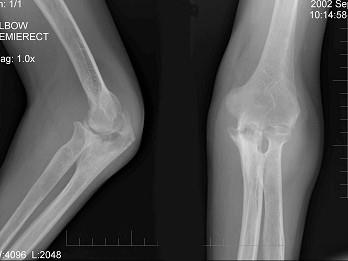

男,61岁,低烧,消廋,胸片示有结核病灶,结合图像,最可能诊断是?(?)A.肘关节结核B.肘关节退行性变C.骨折D.未见异常E.类风湿关节炎

问题 男,61岁,低烧,消廋,胸片示有结核病灶,结合图像,最可能诊断是?(?)

选项 A.肘关节结核 B.肘关节退行性变 C.骨折 D.未见异常 E.类风湿关节炎

答案 A